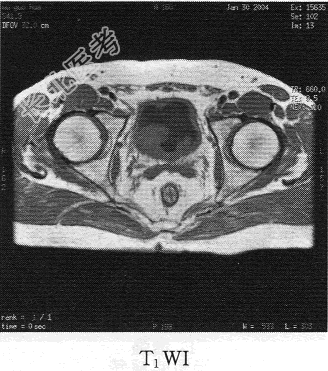

- 单项选择题患者男,76岁。反复无痛性肉眼血尿3个月, MR图像如下,最有可能诊断为

C、膀胱癌